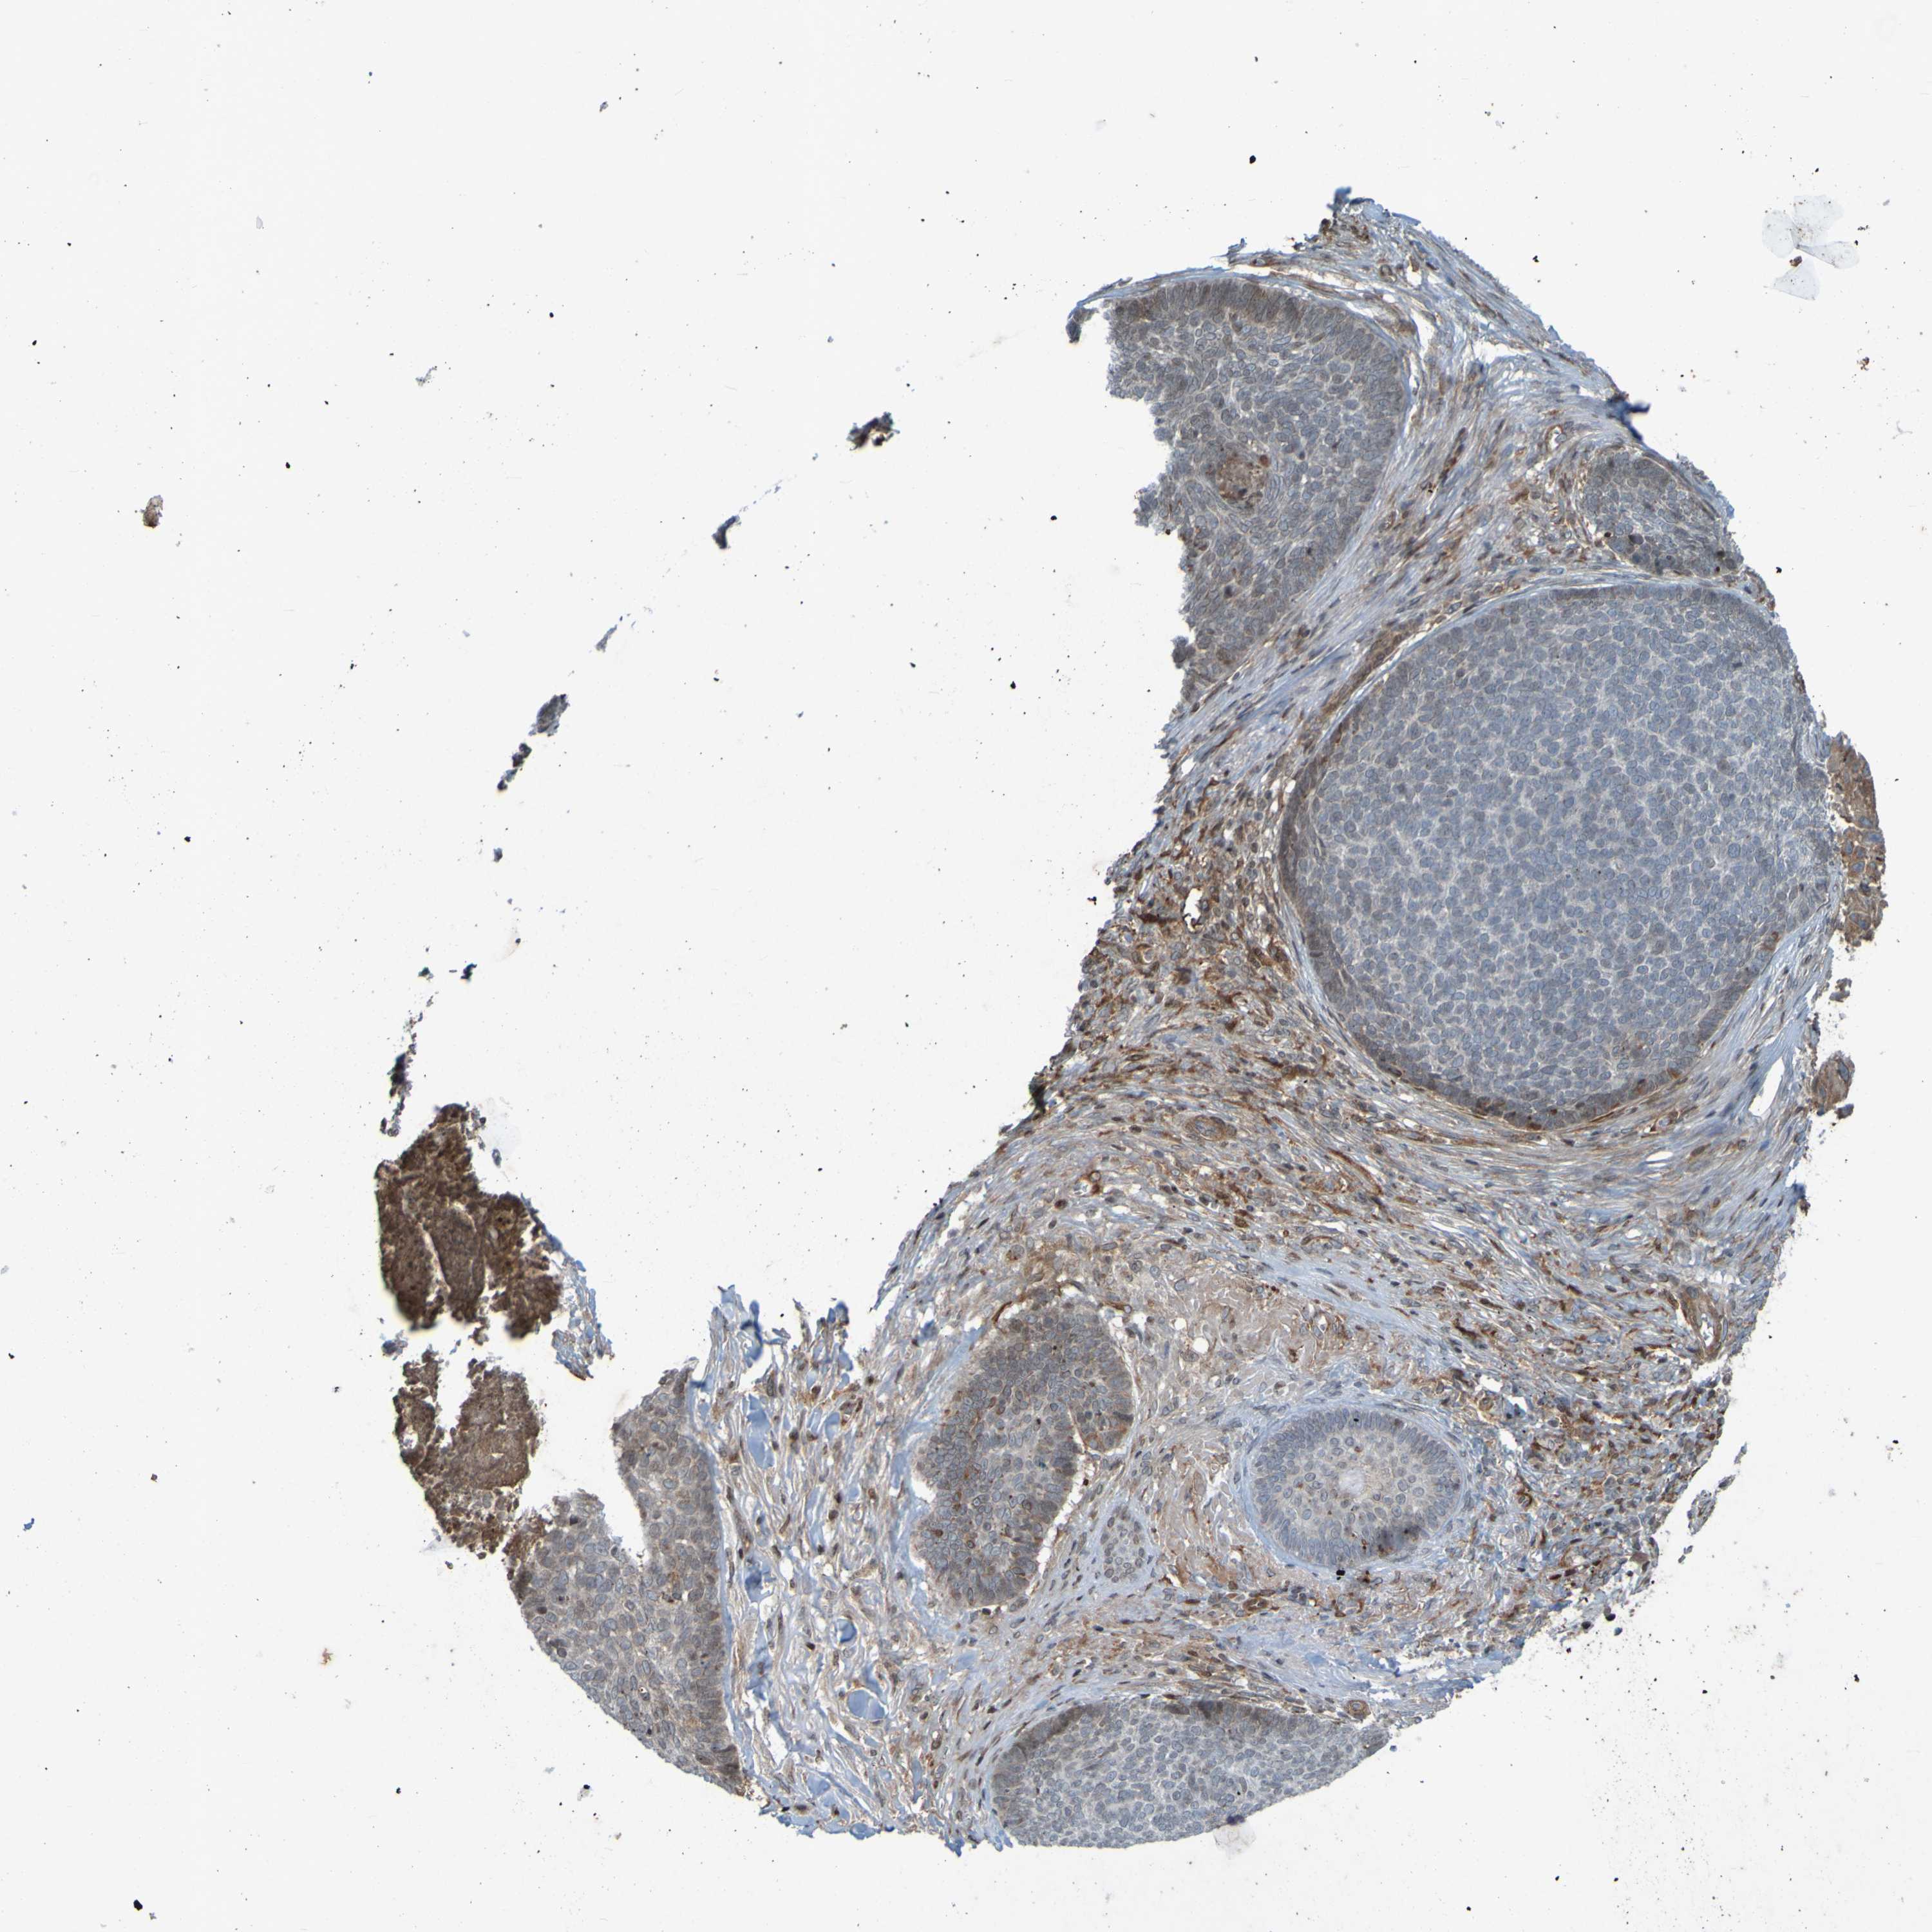

Basal cell and squamous cell cancer

SKIN CANCER - Protein expressioni

A mouse-over function shows sample information and annotation data. Click on an image to view it in a full screen mode. Samples can be filtered based on level of antibody staining by selecting one or several of the following categories: high, medium, low and not detected. The assay and annotation is described here.

Antibody stainingi

Antibody staining in the annotated cell types in the current human tissue is reported as not detected, low, medium, or high, based on conventional immunohistochemistry profiling in selected tissues. This score is based on the combination of the staining intensity and fraction of stained cells.

Each image is clickable and will lead to virtual microscopy that enables deeper exploration of all samples and also displays staining intensity scores, fraction scores and subcellular localization as well as patient and tissue information for each sample.

Antibody CAB010887

Staining

Medium

Intensity

Quantity

Location

Squamous cell carcinoma, NOS

Basal cell carcinoma

Adnexal tumor, benign